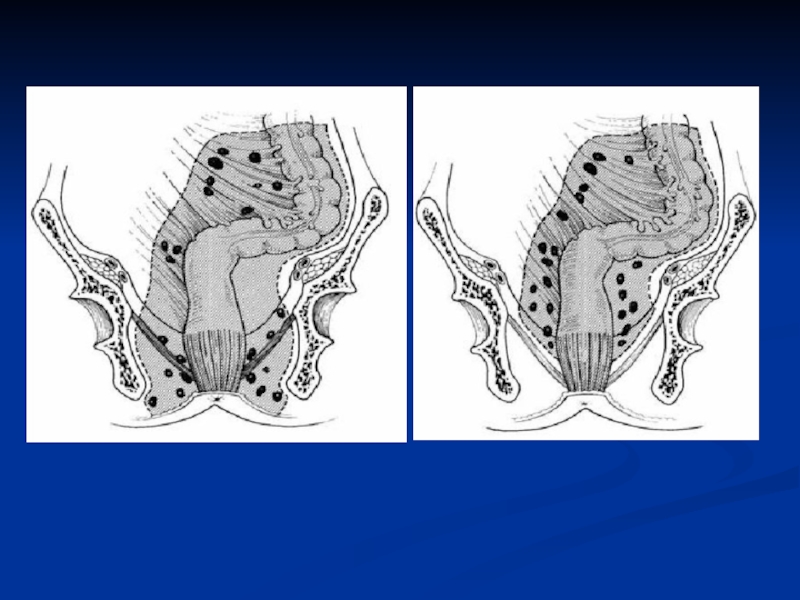

Слайд 48Правосторонняя гемиколэктомия

Правосторонняя гемиколэктомия

Слайд 49Левосторонняя гемиколэктомия

Левосторонняя гемиколэктомия